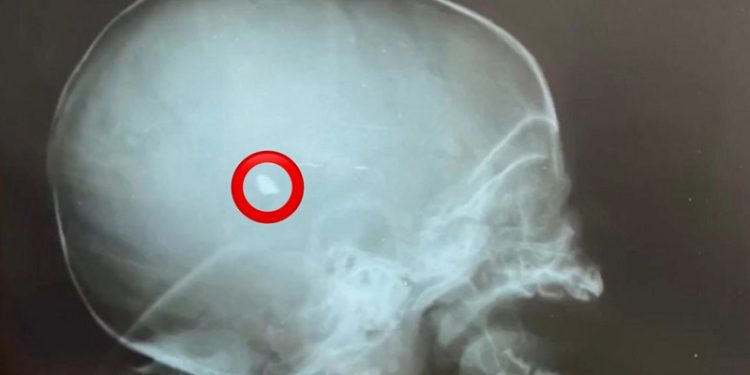

Na noite da última quarta-feira, 04, quatro pessoas foram vítimas de disparos de arma de fogo, enquanto estavam dentro de casa, na Cidade do Povo, em Rio Branco. Entre as vítimas há um recém-nascido, de apenas dois meses de idade, que foi atingido na cabeça e o chumbo está alojado na crânio da criança, que está em estado grave.

Segundo informações repassadas à TV Gazeta, a medicina é quase impossível de reverter a situação e a criança corre sério risco de vida.